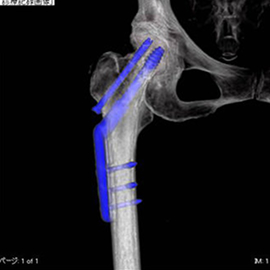

4. 金属アーチファクト抑制技術 (SEMAR)

手術で金属を埋め込まれている患者さんの金属アーチファクトの低減が可能となり、従来は評価しづらかった金属周囲が、より見やすく評価しやすくなりました。

CTの検査画像例